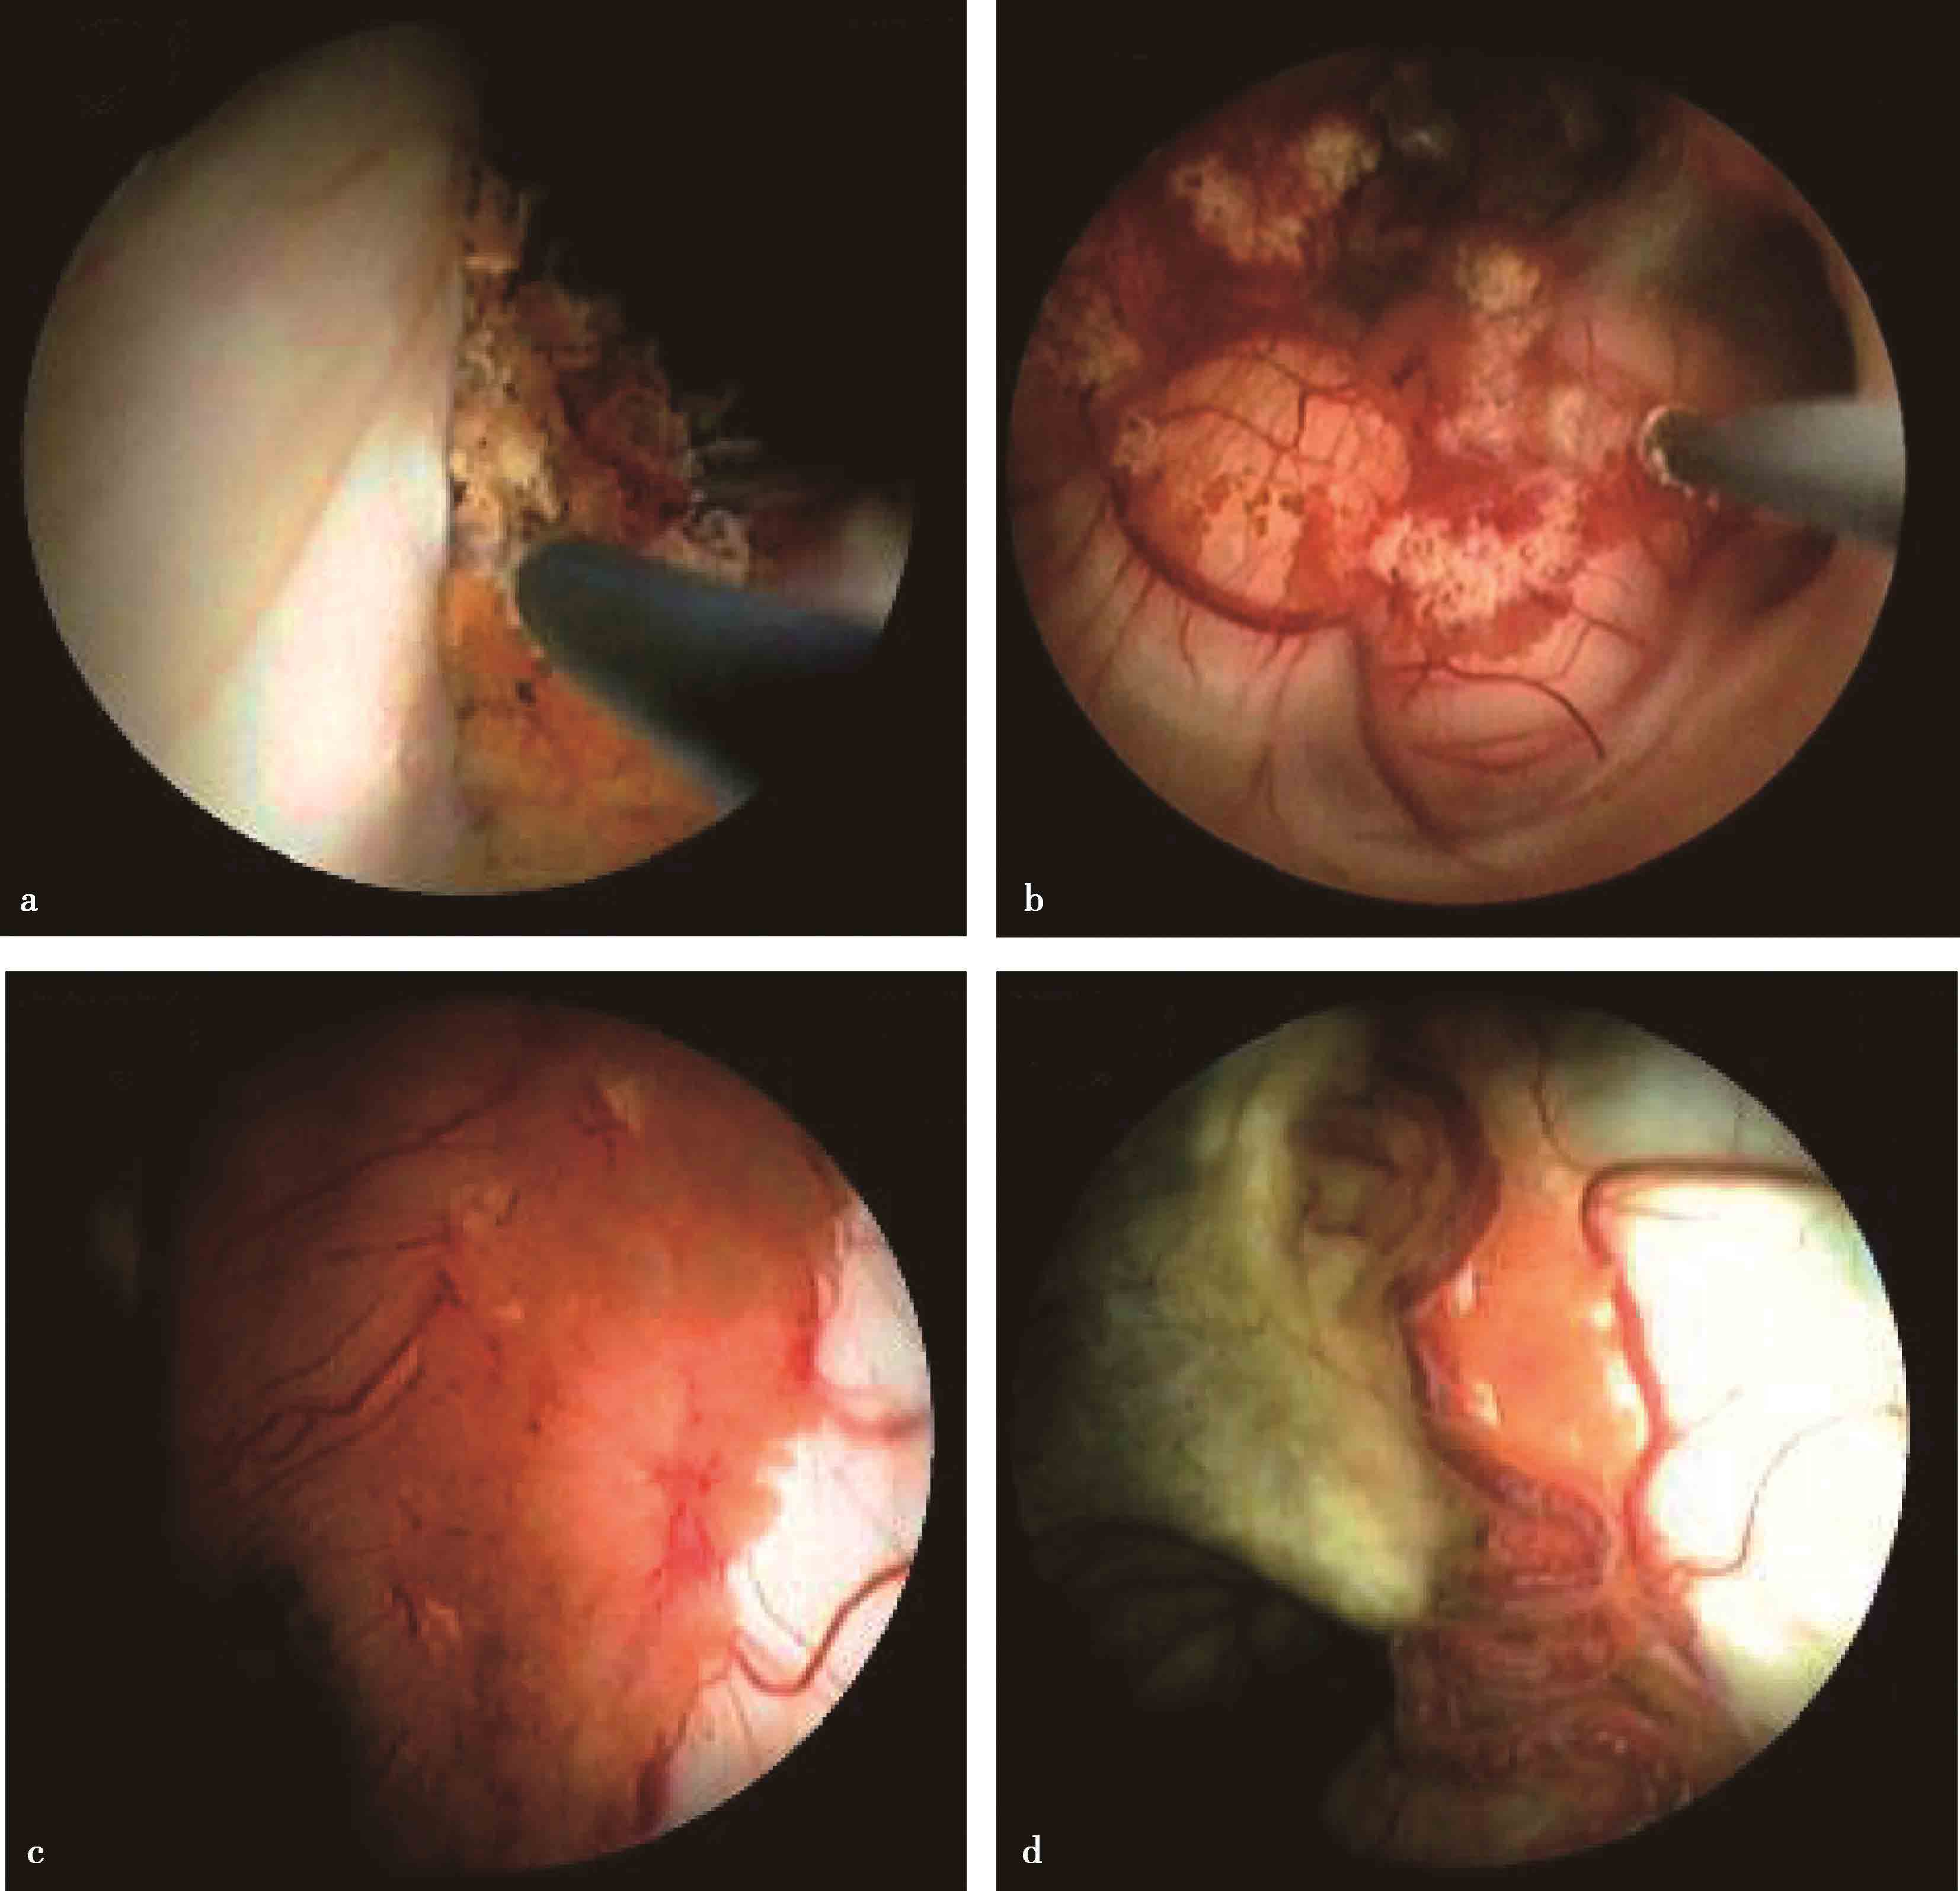

7.脉络丛烧灼术 通过减少脑脊液分泌治疗脑积水。应用软性内镜施行脉络丛烧灼术更为简便,通过额部颅骨钻孔向侧脑室内置入内镜后,经透明隔造瘘口可行双侧脑室脉络丛烧灼,经导水管进行第四脑室脉络丛烧灼,效果更佳(图3-1-2-8)。

图3-1-2-8 内镜下脉络丛烧灼

a.侧脑室脉络丛烧灼;b.第四脑室脉络丛烧灼;c.烧灼前的脉络丛;d.烧灼7个月后,脉络丛明显萎缩